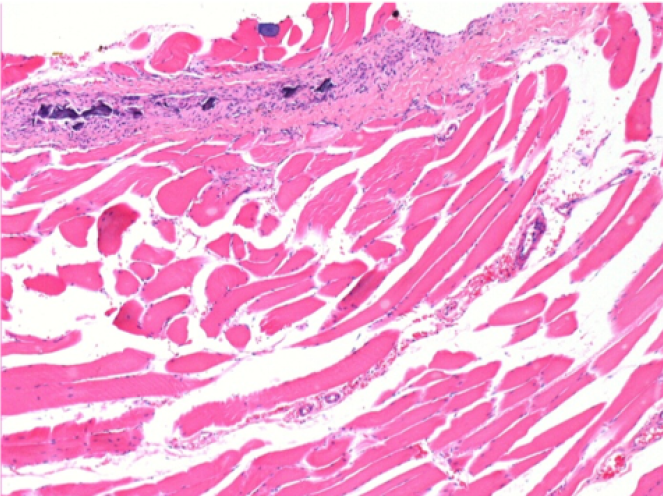

10 days after Endopeel Injection 0.1ml in the right pretibial muscle.

Here you may see the formation of the vacuoles which are surrounded by lymphocytes. Vacuoles are different from tissue necrosis . The presence of lymphocytes is related to the permeability of the cell membranes.